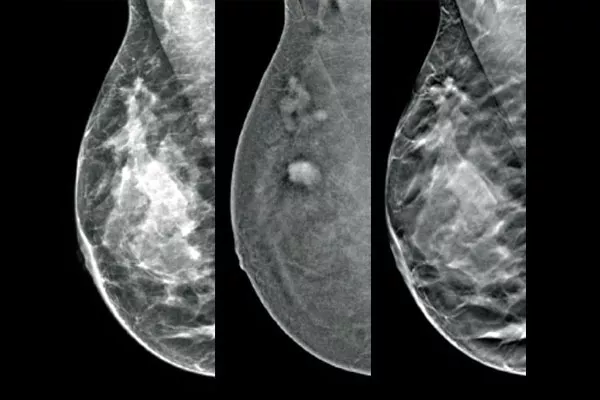

De Affirm® contrastbiopsie solution maakt de targeting en het verkrijgen van borstweefsel mogelijk in laesies die zijn geïdentificeerd tijdens contrastversterkte mammografie (CEM). De complete contrastbiopsie solution is ontworpen om de efficiëntie van de workflow te maximaliseren, tegelijkertijd de ervaring van de patiënt te verbeteren en het borstbiopsieproces te vereenvoudigen,* ook bij lastige procedures.

Target en neem een biopsie af van met 2D-contrastversterkte mammografie geïdentificeerd laesies door middel van een stereotactische procedure, met vergelijkbare diagnostische prestaties als bij een borst-MRI-procedure.1,2 Vergelijk post-marker-beelden in dezelfde modaliteit als het initiële diagnostische contrastonderzoek.

Met Affirm software voor contrastbiopsie kunt u een biopsie uitvoeren op laesies die zijn geïdentificeerd tijdens de I-View™ contrastversterkte 2D-mammografie. Door gebruik te maken van de mogelijkheid om 2D-, contrastversterkte en tomosynthese-afbeeldingen te bieden onder één compressie,4 maakt het Affirm upright geleidingssysteem voor borstbiopsie een snelle overgang van screening naar biopsie mogelijk, door gebruik te maken van dezelfde beproefde beeldvormingsketen5 als het mammografiesysteem om 3D™ visualisatie van verdachte laesies te verbeteren.**

Een efficiënt en kosteneffectief alternatief voor MRI

Functionele beeldvorming met gebruik van CEM doet het goed in vergelijking met een borst-MRI, met vergelijkbare gevoeligheid, hogere specificiteit en een hogere positieve voorspellende waarde.7,8 Bovendien biedt CEM een kosteneffectief alternatief voor diagnostische beeldvorming9 ten opzichte van MRI, met een kortere proceduretijd.7,10